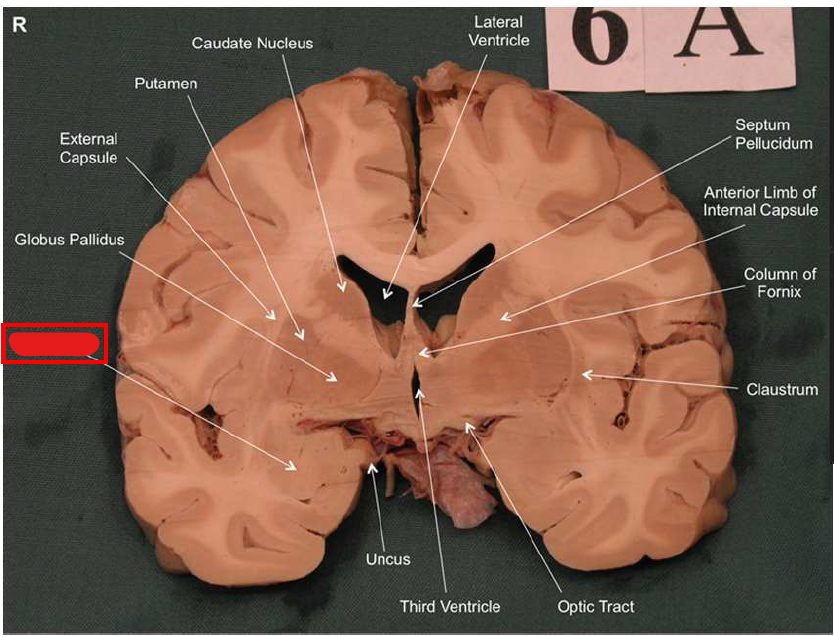

What is the function of the amygdala?

Emotions & Memory Hub

Processes emotions (esp. fear & pleasure)

Helps us remember emotional experiences

Imagine the amygdala as a fire alarm in your brain. When it senses danger (fire!), it triggers the alarm (fight-or-flight response) almost instantaneously and remembers the event vividly (emotional memory)

Stimulation of _ via the ipsilateral frontal cortex elicits aggression

amygdala

What is Kluver-Bucy syndrome?

Rare brain disorder caused by bilateral lesion of the amygdala. Due to lobectomies, encephalitis from Herpes simplex, stroke, or Alzhemier’s. Causes abnormal behaviors and memory problems:

Putting objects in mouth (hyperorality)

Excessive touching of objects (hypermetamorphosis)

Increased sex drive (hypersexuality)

Binge eating/purging (bulimia)

Difficulty recognizing objects (visual agnosia)

Memory problems (amnesia)